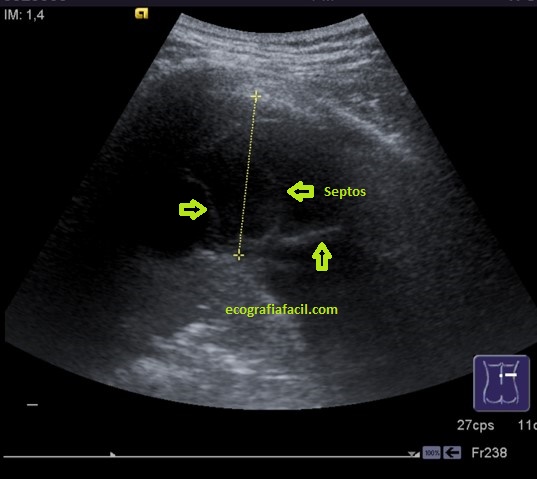

En esta primera imagen vemos una cámara líquida correspondiente a un derrame pleural y las medidas estándar que realizamos como información previa a la Toracocentesis.

In this first image we see a liquid chamber corresponding to a pleural effusion and the standard measurements that we made as prior information to the Toracocentesis.

En algunas ocasiones cuando el derrame evoluciona negativamente, podemos ver septos en su interior, como imágenes hiperecogénicas lineales dentro de la cámara.

On some occasions when the effusion evolves negatively, we can see septa inside it, as linear hyperechoic images inside the camera.